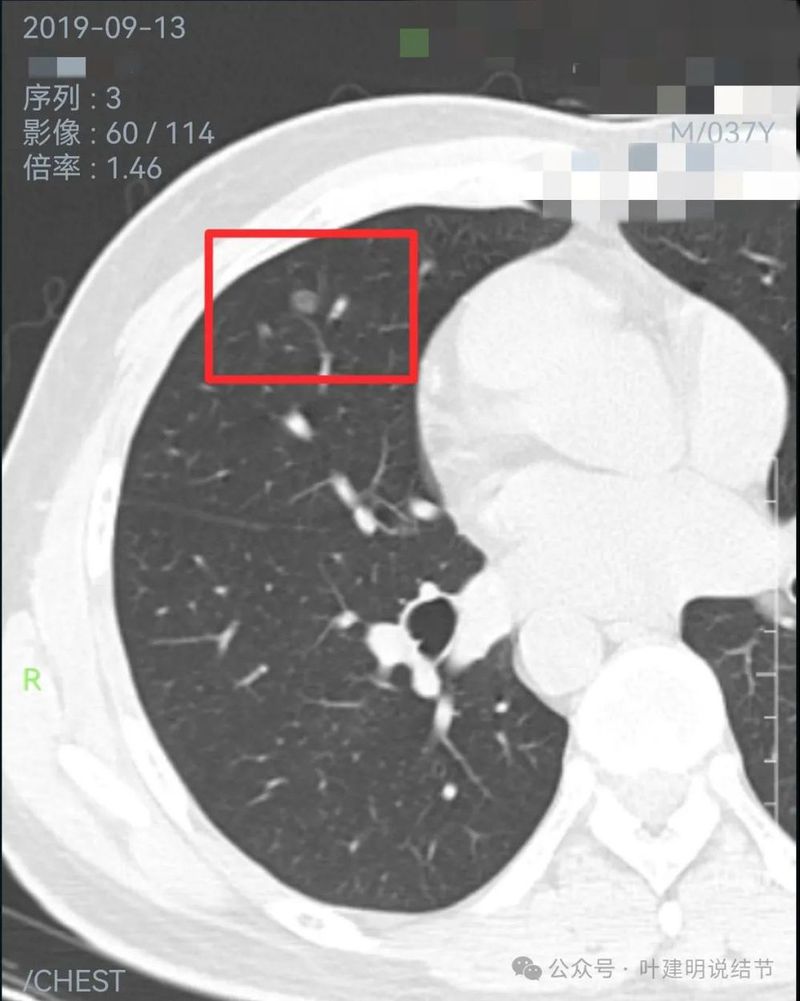

2019年9月时右中叶磨玻璃密度病灶,轮廓与边界清楚,没有实性成分,中间密度稍低,考虑肿瘤范畴的,原位癌或微浸润性腺癌可能性较大。